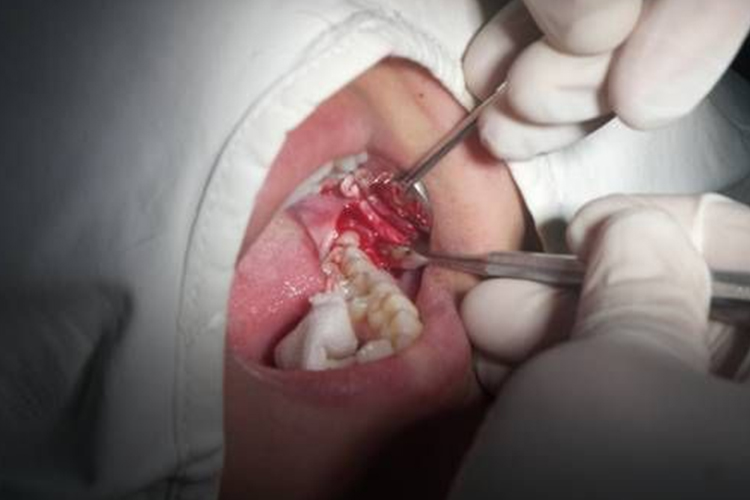

切开软组织及翻瓣

拔牙前应彻底冲洗盲袋,切开翻瓣后还应进一步冲洗。高位阻生一般不需翻瓣,或仅切开及分离覆盖在表面的软组织以解除阻力。如牙未完全萌出,需作远中切口及颊侧切口远中切口,然后用薄的骨膜分离器直抵骨面,紧贴骨面向后向颊侧将瓣掀开。